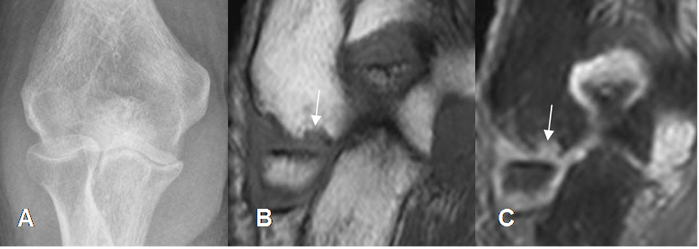

Fig 8. Lesión osteocondral

A: Rx AP. Osteopenia difusa por artritis reumatoidea, con disminución de los espacios articulares.

B: RM coronal en T1 y C: RM coronal en STIR. Lesión osteocondral del epicóndilo lateral, con erosión y alteración de la señal.